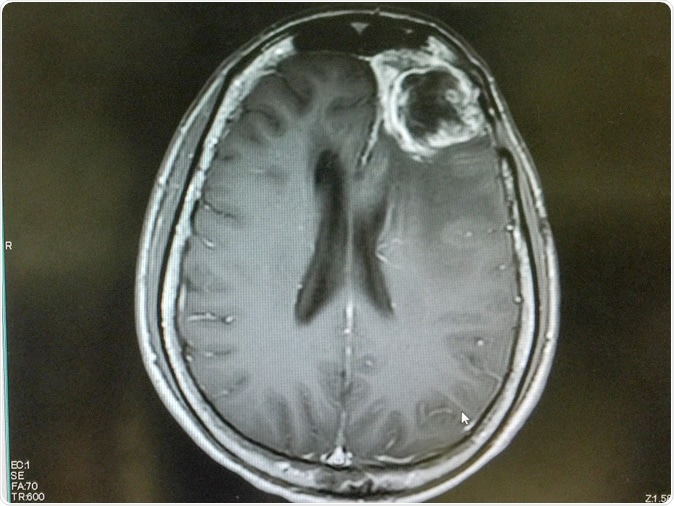

MRI of brain showing left frontal gliblastoma. Image Credit: O_Akira / Shutterstock